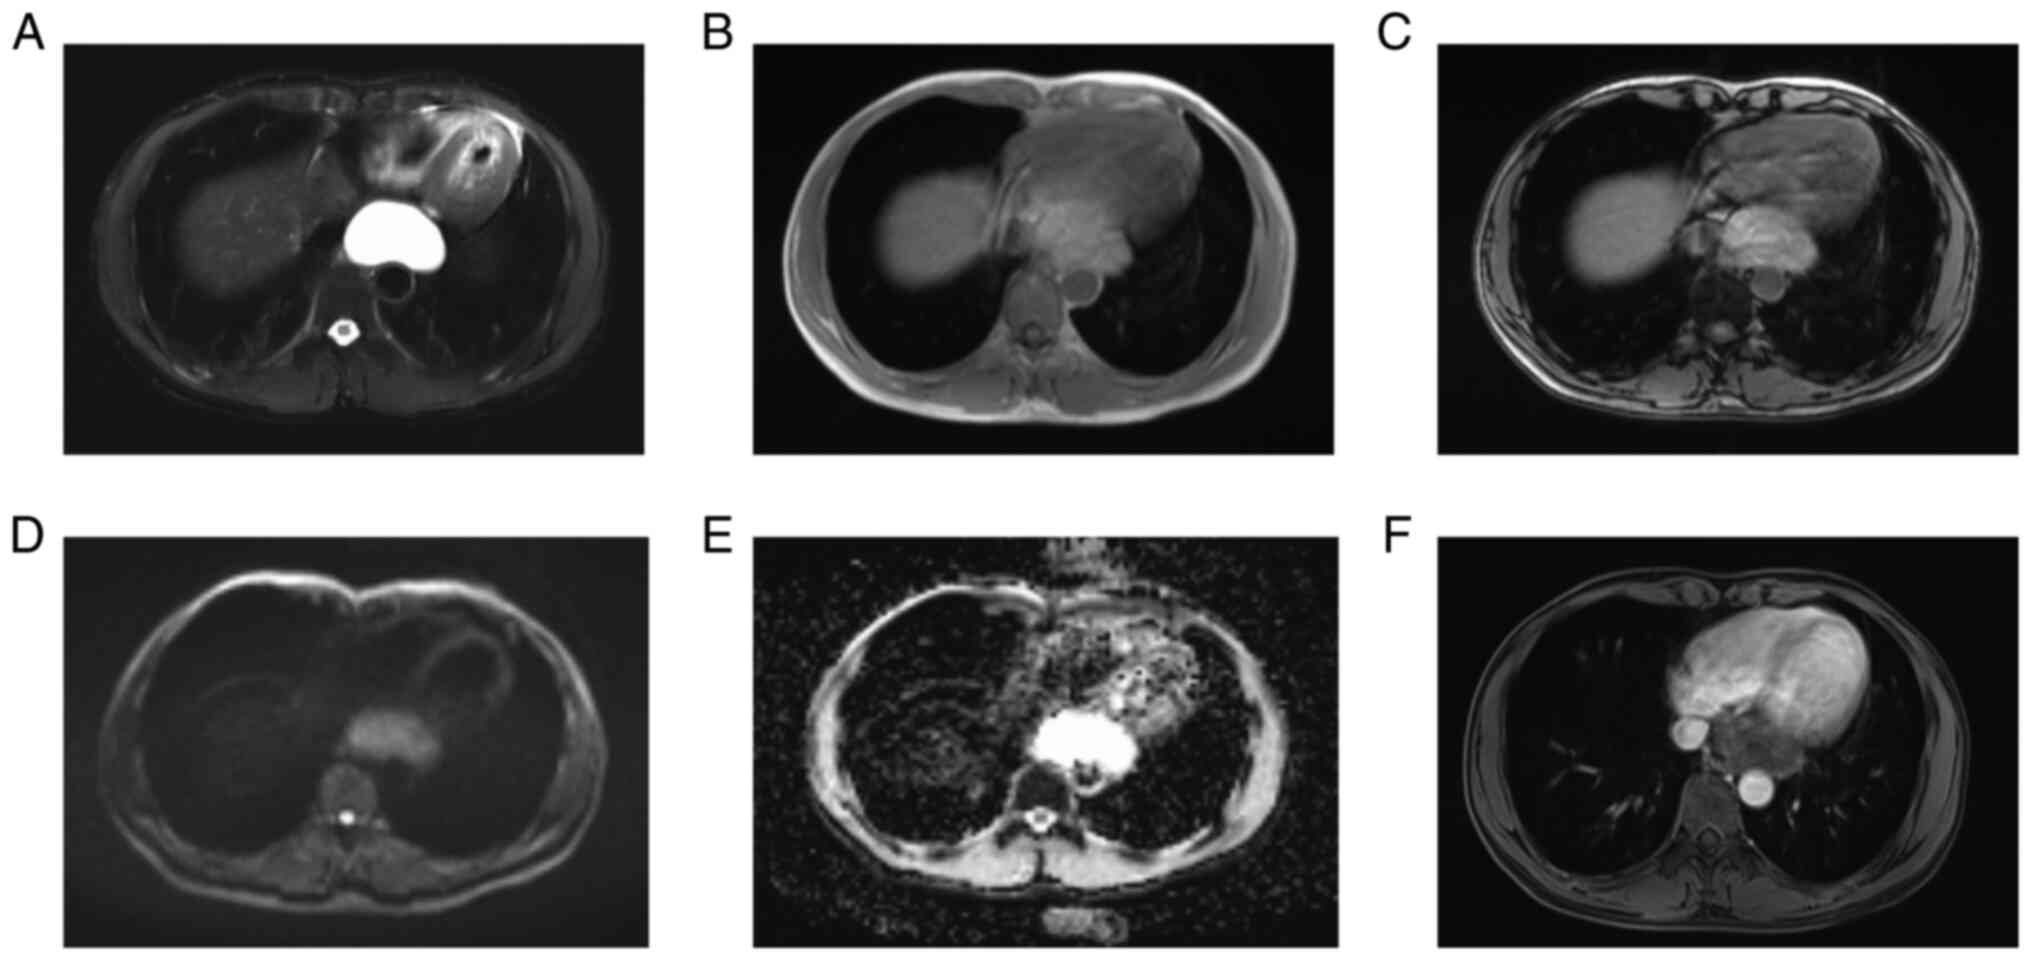

1). Plain and enhanced mediastinal magnetic resonance imaging

(MRI) revealed a lumpy abnormal signal shadow in the posterior

mediastinum, with a clear boundary of ~6.0x4.0x5.2 cm,

hyperintensity on T2-weighted imaging, iso-slight hyperintensity on

T1-weighted imaging, a slightly increased signal on reverse phase,

a slightly higher signal on diffusion-weighted imaging, obvious

hyperintensity on apparent diffusion coefficients mapping, no

obvious enhancement overall and suspicious slight enhancement on

the edge, which further supported that the cystic mass was a benign

lesion, most likely a cyst (Fig.

2). The upper gastrointestinal barium contrast indicated that